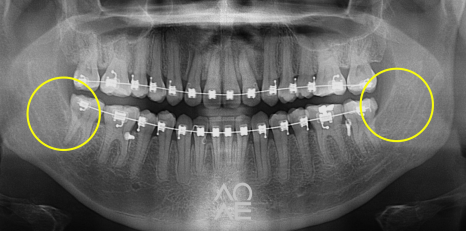

당일 발치를 진행하였습니다

24.6.29

5분만에 발치하였습니다!

이번 발치 케이스도, 최소 침습과 최단 시간

발치로 깔끔하게 해결해드렸습니다!

| 발치 전 | 발치 후 |